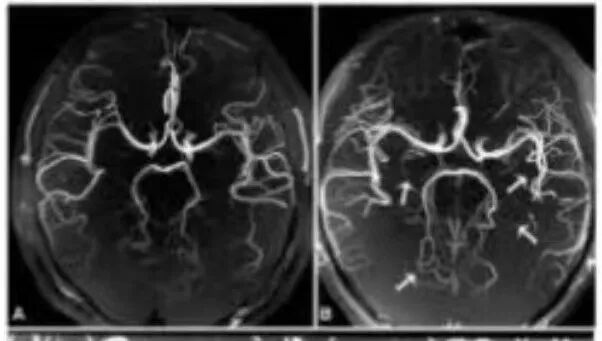

CT与磁共振成像原理及特点 CT检查是利用X线穿透人体后,通过探测器收集数据,再由计算机重建出人体内部结构的图像。它具有成像速度快、密度分辨率高的特点,能够快速发现颅内出血、骨折等病变。然而,CT检查存在一定的局限性,比如对软组织的分辨率较低,且由于颅骨的干扰,后脑病变的显示效果不佳。如果要显示脑血管,需要注射造影剂。 磁共振成像是一种无辐射的检查技术,通过强大的磁场和无线电波脉冲,利用人体内不同组织的磁化反应来成像。它具有多方位、多参数成像的特点,能够提供丰富的组织对比度和详细的解剖信息。磁共振检查在软组织分辨率、图像立体观和抗骨性干扰等方面具有显著优势。 磁共振对后脑病灶显示的优势 后颅窝是脑部的一个重要区域,包括小脑、脑干等重要结构。由于其位置较深,且周围有颅骨的遮挡,CT检查在显示后颅窝病变时往往受到限制。而磁共振检查则能够很好地弥补这一不足。此外,磁共振对软组织的分辨率极高,能够清晰显示小脑、脑干等部位的病变,如脑梗死、肿瘤、脑干病变等。此外磁共振DWI序列能在脑梗死后发生后数分钟就可以发现病灶,而CT需要发病后6-24小时才能发现病灶。尤其是症状表现为头晕,眩晕的患者推荐磁共振检查。 图例: 72岁,男性,突发右侧偏瘫,左侧面瘫,言语含混6小时,CT未见异常,磁共振显示左侧桥脑腹外侧脑梗死。 磁共振评估颅内血管的优势 磁共振血管成像(MRA)是磁共振技术在血管检查中的重要应用。它是一种无创性检查方法,无需注射造影剂,即可获得高分辨率的血管影像。这使得MRA特别适合长期随访的患者以及对造影剂过敏的人群。MRA能够清晰显示颅内动脉的狭窄、闭塞、动脉瘤、动静脉畸形等病变。